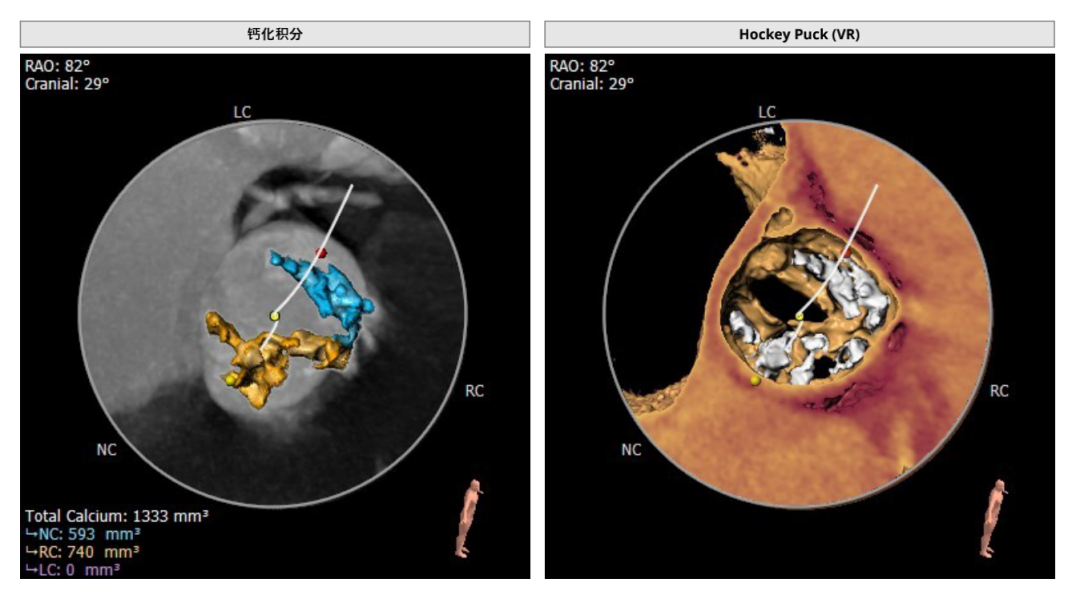

钙化积分及分布

该患者为二叶式畸形主动脉瓣极重度钙化,钙化积分高达1333,且在左右冠窦交界处存在钙化粘连,瓣膜下滑风险增加,球扩时瓣环撕裂风险增加;

该患者为TYPE1型二叶瓣,且主动脉瓣极重度钙化,钙化积分高达1351,瓣膜移位风险增加。

患者左右窦之间存在钙化融合,融合脊较难推动,且瓣口打开呈椭圆形,可能出现瓣中瓣无法解决的瓣周漏。